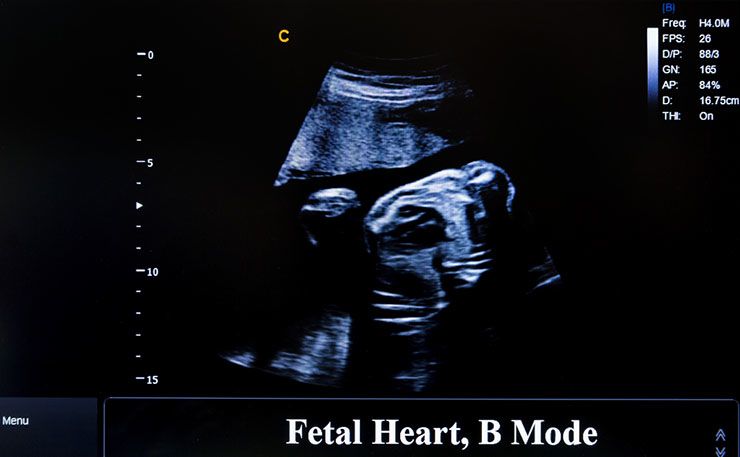

Girl Born Without Proper Organ Gives Birth In Bizarre And Miraculous Pregnancy